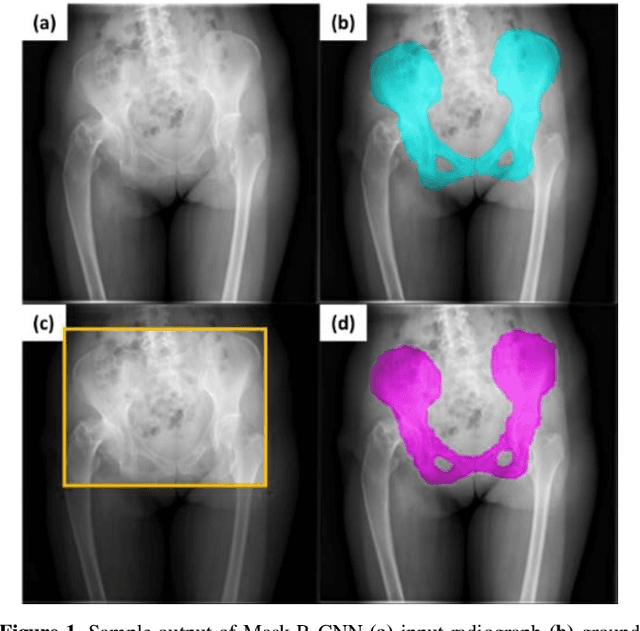

Abstract:With the increasing usage of radiograph images as a most common medical imaging system for diagnosis, treatment planning, and clinical studies, it is increasingly becoming a vital factor to use machine learning-based systems to provide reliable information for surgical pre-planning. Segmentation of pelvic bone in radiograph images is a critical preprocessing step for some applications such as automatic pose estimation and disease detection. However, the encoder-decoder style network known as U-Net has demonstrated limited results due to the challenging complexity of the pelvic shapes, especially in severe patients. In this paper, we propose a novel multi-task segmentation method based on Mask R-CNN architecture. For training, the network weights were initialized by large non-medical dataset and fine-tuned with radiograph images. Furthermore, in the training process, augmented data was generated to improve network performance. Our experiments show that Mask R-CNN utilizing multi-task learning, transfer learning, and data augmentation techniques achieve 0.96 DICE coefficient, which significantly outperforms the U-Net. Notably, for a fair comparison, the same transfer learning and data augmentation techniques have been used for U-net training.